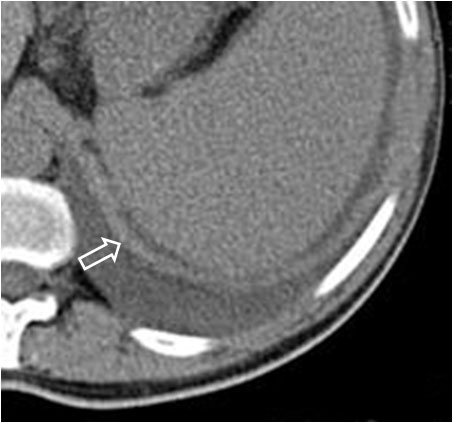

Cuando en la TC vemos líquido en situación dorsal al hígado (flecha), éste se encuentra en la cavidad pleural, ya que el líquido intraperitoneal no puede acumularse en esta zona debido a que el peritoneo se repliega sobre la cúpula hepática sin llegar a cubrir la parte posterior del hígado, es decir, que no hay cavidad peritoneal por detrás del hígado y, por tanto, la ascitis no puede ocupar este espacio.

En esta imagen también está presente, lógicamente, el Signo de la interfase.

En la imagen correspondiente a ascitis que presentamos en el signo anterior, observa cómo se respeta la zona posteromedial del hígado.